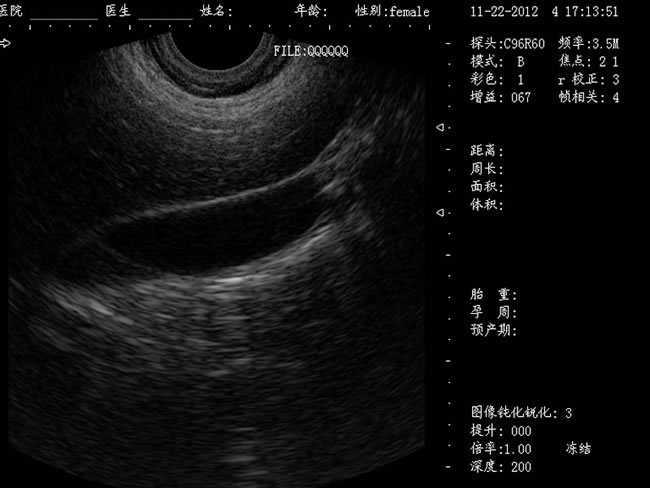

DW-400

功能特點:

定位精確 手術效率高:實時動態頻率掃描等全數字超聲成像技術、生成精確的圖像引導手術器械迅速到大手術位置,避免損傷子宮內膜和子宮穿孔的現象,即減輕了患者的痛苦又極大提高了手術效率。

高密度全數字波束形成:采用全新一代混頻技術、數字嵌入系統及數字整序技術

有效提升系統的穩定性、可靠性:實時動態孔徑成像,充分保證圖像的精度和清晰度

標準配置:

主機

CXA10R/6.5MHz 腔內探頭

12.1英寸LED液晶顯示器

擴陰器

選配:CXA60R/3.5MHz 凸陣探頭

隨著醫療技術水平的提高,目前婦產科手術中所應用的相關設備也有了加大的改進。尤其是在人工流產手術中,將B超婦產科手術監視儀應用到手術過程中,彌補傳統手術中所采用設備的不足之處,減輕手術中患者的疼痛感覺,使得手術順利的完成。這種儀器相比于傳統的儀器來說,其在操作上更為方便和簡單,能夠對妊娠反應有很好的療效。